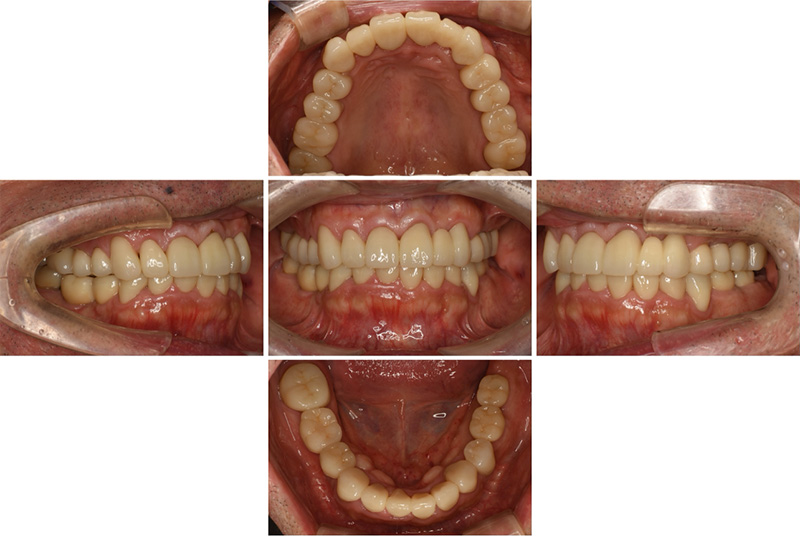

58歳女性

治療前

治療後

| 施術名 | インプラント治療 |

| 施術の説明 | インプラント治療とは、歯を抜いた所にチタン製の人工歯根を埋入し、新しく歯を入れる方法です。 |

| 施術の副作用 (リスク) | 腫れや疼痛を感じる、違和感を感じるなどの症状を生じることがあります。 |

| 施術の価格 | 53万円~+消費税 |